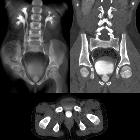

CT

CT can delineate all abnormalities essentially, especially when performed during the excretory (IVP) phase (contrast outlining the collecting systems). CT reconstruction software can produce striking single images of the collecting systems. In an unobstructed system, the diagnosis can be difficult. A duplicated renal collecting system can be suspected by identifying the so-called faceless kidney.